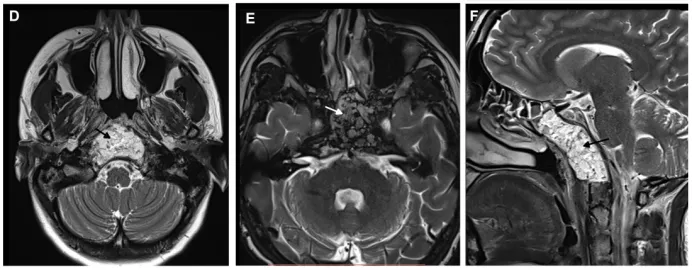

从右侧蝶窦水平到鼻后孔垂直切开鼻腔粘膜,鼻腔粘膜部分分离,打开蝶窦。进一步磨骨暴露斜坡,并显露肿瘤的侧下部分。根据术中肿瘤、术野情况,使用角度为30°、45°和70°的内镜以及弯曲和可弯曲的器械切除肿瘤。肿瘤切除后,切除浸润的蝶窦粘膜。

然后开始颅底重建,在瘤腔内和蝶窦内放置脂肪移植物。由于切口边缘有的缩回,无法进行水密缝合,因此将切口右侧边缘与左鼻中隔粘膜缝合(粘膜II型缝合技术)。

定位识别蝶窦,并用手术纤维胶覆盖。

术后MRI证实肿瘤完全切除。在2个月的随访中,内镜检查没有发现结痂,患者也没有抱怨任何鼻腔不适。

▼术后MRI显示肿瘤全切,鼻窝完整。箭头所指为术后用于填充残腔的脂肪。